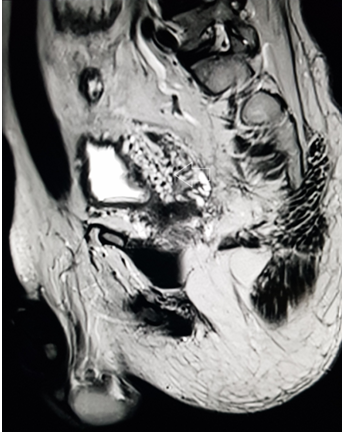

A 39 year old male presented with the chief complaint of pelvic discomfort and on and off haematuria. It was not associated with fever or urinary retention. No bowel symptoms were noted. Patient had history of paralytic poliomyelitis in his childhood and walked with crutches. On laboratory examination, patient was found to have deranged renal function tests with elevated creatinine level. Hence, we conducted MRI pelvis with MR urography to look for the urinary systemand to look for the status of the the pelvic muscles and joints. MR study showed multiple tortuous dilated vessels on the right side of pelvis suggestive of pelvic arteriovenous malformation (Figure 1&2). The arterial supply was noted from multiple branches of the right internal iliac artery and venous drainage was noted into right external iliac vein and deep external pudendal vein. The tangle of vessels was abutting the right lateral wall of urinary bladder, prostate and right seminal vesicle medially (Figure 1&3). It was abutting the obturatorinternus muscle laterally. There wasasymmetric thickening of the right lateral wall of urinary bladder adjacent to the vascular malformation (Figure 1). It was not associated with perivesicular fat strandings or enlarged locoregional lymphnodes. No restriction of diffusion was noted in DWI images. Prostate and bilateral bilateral seminal vesicles were normal in signal intensity and morphology. As a sequalae of childhood poliomyelitis, diffuse atrophy of pelvic muscles was noted that was more prominent on the right side (Figure 4&5). T1 and T2 high signal intensity suggestive of fatty replacement was noted in bilateral psoas and right obturaterinternus mucle. Fatty atrophy of bilateral hip and proximal thigh muscles were also seen (Figure 5). Abduction and external rotation was noted at bilateral hip joints (Figure 4). Histological examination of the bladder wall revealed polypoid bladder mucosa with chronic inflammation consistent with polypoid cystitis. Arteriovenous malformation was managed with intra-arterial coil embolization and subsequently the patient’s symptoms improved.

Figure 3 MRI sagittalT2 weighted image through the pelvis demonstrate multiple tangle of vessels (white arrow) on the right posterolateral aspect of urinary bladder.